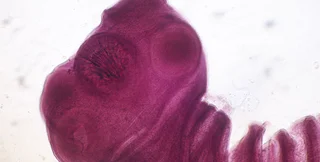

Свиные цепни способны проникать в мозг человека | Фото: Wikipedia

Известно, что Кеннеди-младший страдал от когнитивных проблем, а врачи изначально подозревали у него опухоль мозга. После оказалось, что он болен паразитарной инфекцией — в его мозгу поселилась личинка свиного цепня (Taenia solium). Отметим, что эти паразиты встречаются в странах с низким уровнем дохода, где люди живут рядом с домашним скотом, в том числе:

Как только ленточный червь прикрепляется к стенке кишечника человека с помощью крючков и присосок, он растет и созревает, поглощая питательные вещества в человеческом кишечнике. По мере взросления червь образует сотни сегментов, известных как "проглоттиды", длиной в несколько миллиметров. При этом сам червь может достичь невероятных 4 метров в длину.

Оказавшись в желудке и кишечнике животного, ферменты высвобождают цистицерки из внешних оболочек, в результате чего они способны проникать в ткани свиней, где вызывают активную инфекцию — цистицеркоз. Ученые обнаружили, что личинки способны проникать во все основные органы свиньи, в том числе печень, почки, легкие и даже мозг.